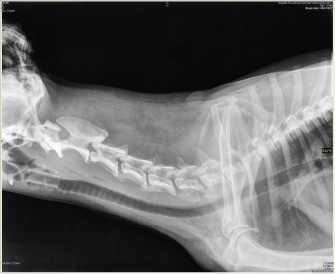

After the procedure, depending on the clinical condition and the owner’s choice, the dog could go home or remain in hospital. Two to three hours after the procedure, water can be offered. If the dog does not cough while drinking, the stent is perfectly placed. If the dog coughs while drinking, wet food should be offered until the stent is accommodated properly by the swallowing reflex itself. The stent is visible by X-ray as shown in Fig. 3.

Fig. 3. Neck latero-lateral X-ray: correct position of the laryngeal stent.